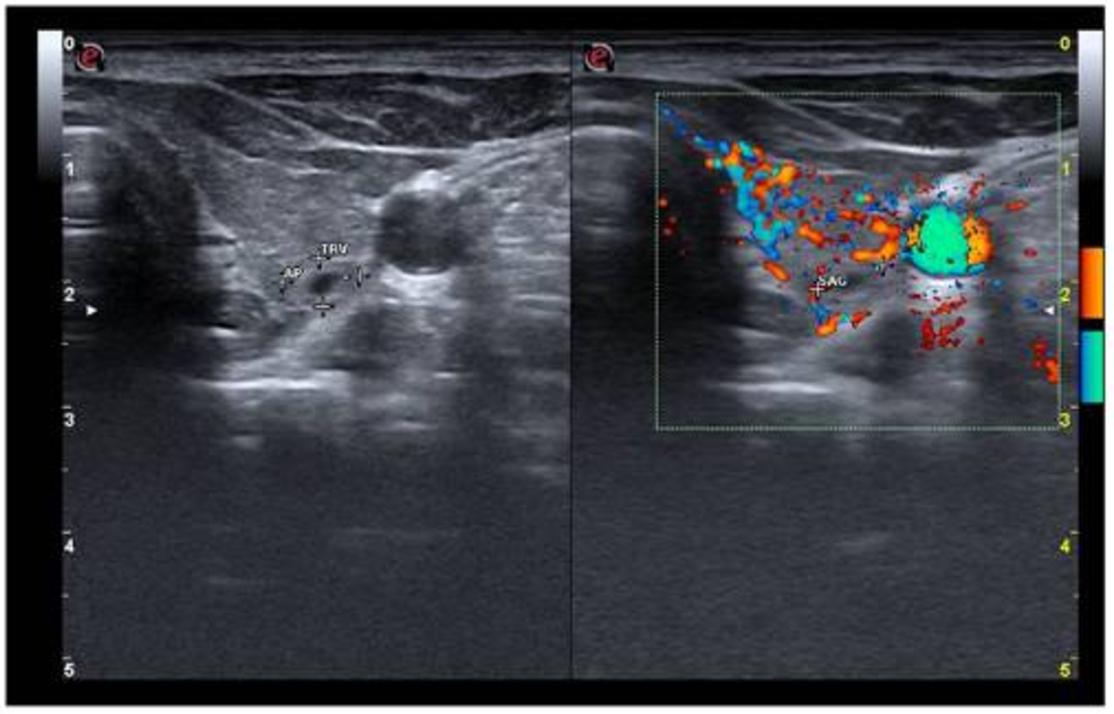

颈部超声检查见甲状腺实质低回声,甲状腺体积增加(26.8 ml,正常上限<16 ml)。右叶被海绵状结节完全取代,血管增加(图1),ACR-TIRADS将其归类为良性(2级)。左叶血管增多,见一个6/5/7mm的部分囊性结节(图2),ACR-TIRADS也将其归类为良性(2级)。

图1 甲状腺右叶被海绵状结节(横切面)替代